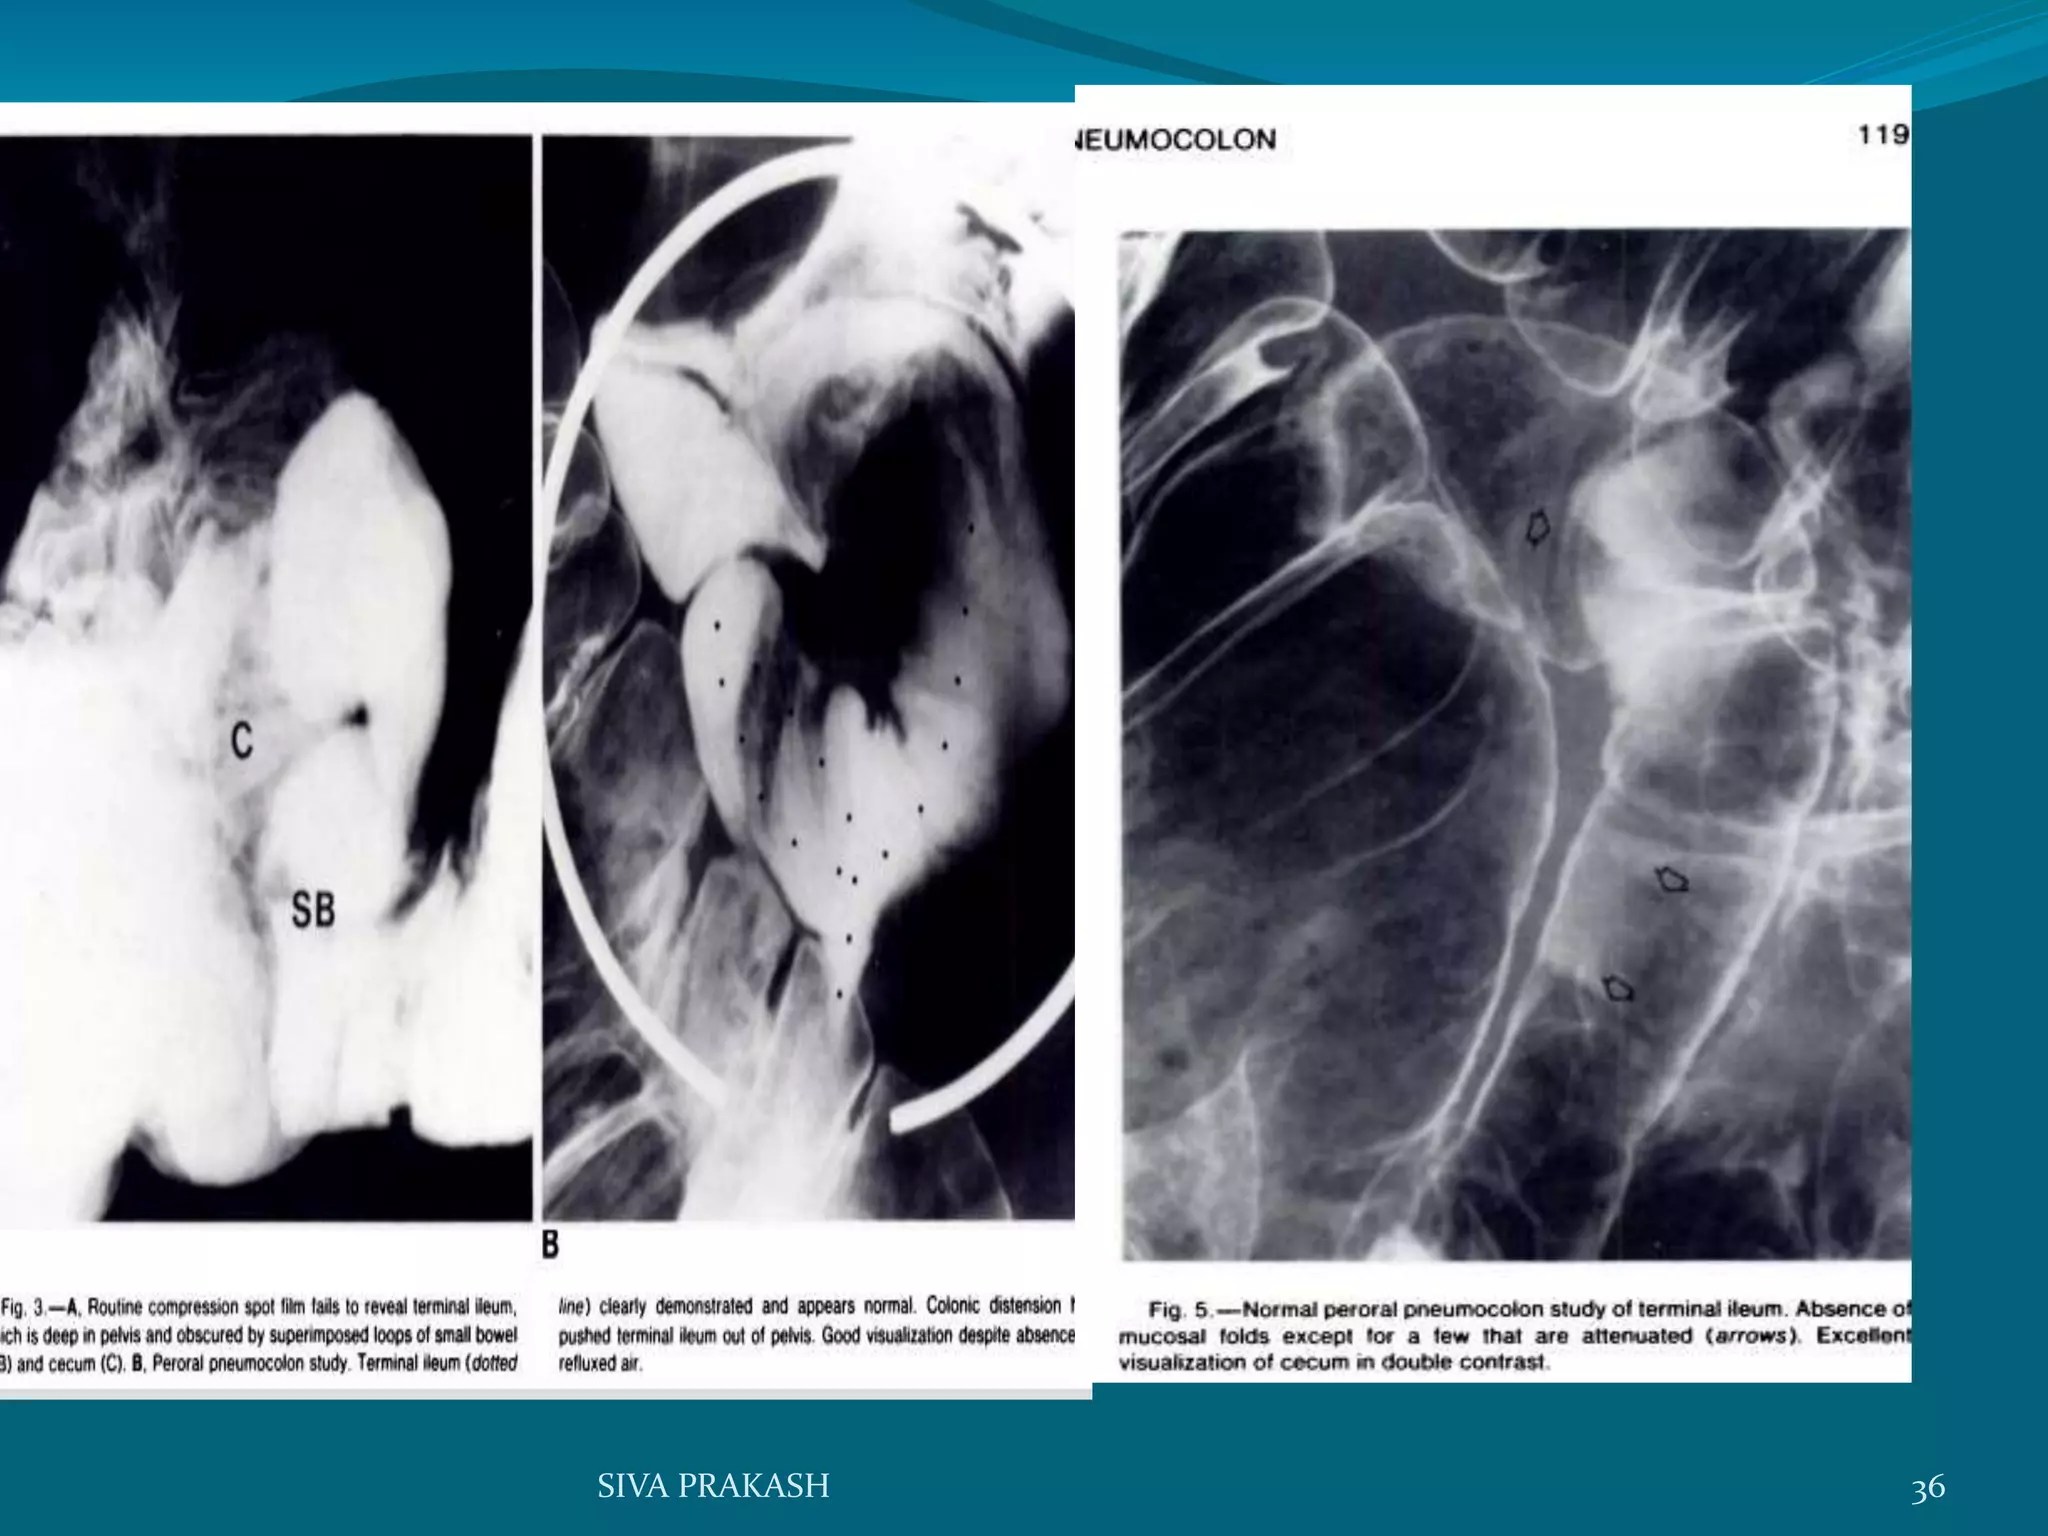

Peroral Pneumocolon examination

 Excellent view of the terminal ileum and caecum can

be obtained by giving barium orally and when the

head of the barium column has reached the ascending

colon introducing air per rectum and refluxed in to

distal ileum

 Glucagon can be used to relax ileocaecal valve

 This procedure shows Crohn’s disease and carcinoma

of the caecum particularly well

Per oral pneumocolon

examination

Indications contraindicatns

 Terminal ileum porly

visualized on routine

compresion spot films .

 Clinical suspicon of Crohn

disease with normal

apearance of terminal ileum

 abnormal apearance of

terminal ileum on routine

compresion spot films

 history ileocolic

anastomosis.

 Recent colonic or rectal

biopsy

35SIVA PRAKASH

36SIVA PRAKASH